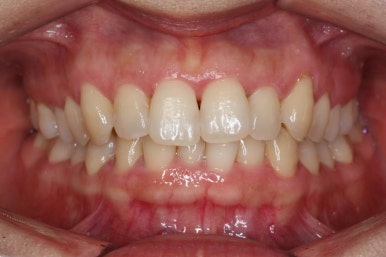

부산설측교정 키다리아저씨치과에서 처음 내원하셨을 당시의 얼굴 모습입니다.

입술도 편안하게 물리고 옆 모습 라인도 좋습니다.

다만, 웃을 때 앞니 치열이 삐뚤어서 보기에 좀 좋지 않은 상황이었습니다.

마찬가지로 부산설측교정 키다리아저씨치과에서 처음 내원하셨을 당시의 입안 모습입니다.

어금니쪽은 특별히 이상이 없었고, 위아래 앞니만 삐뚤한 상태였습니다.